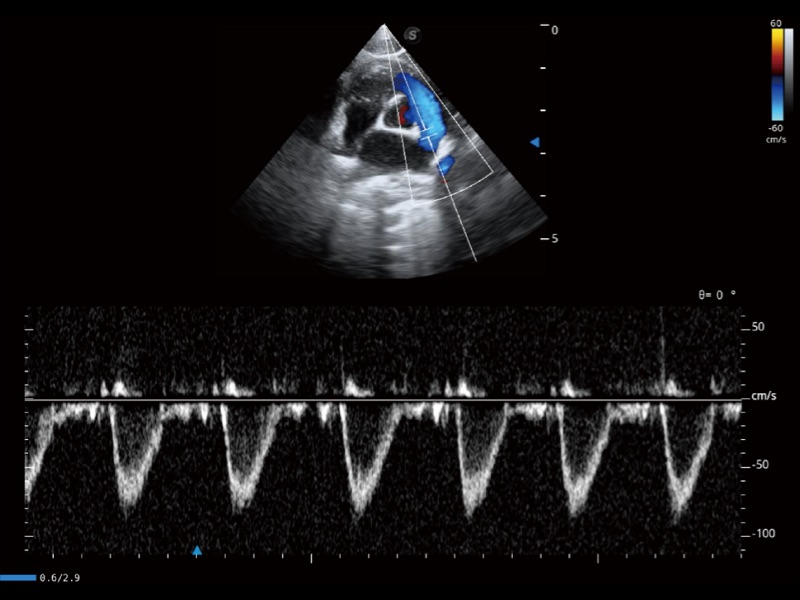

(猫)肺动脉血流频谱

• AMM 解剖M型

通过360度任意调节3条M型取样线,在同一心动周期上观察心脏不同位置的运动曲线,得到准确的心功能测量数据,有效评估心肌运动及左心室功能。